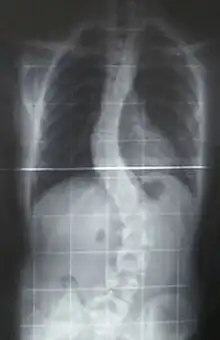

- CMD with spinal rigidity present at birth can have poor muscle tone and weakness, reduced respiratory capacity, muscles could be deformed, beginning early ages stabilization or slow decline spinal rigidity, limited mobility to flex the neck and spine, spinal curvature and progressing deformity and rigidity joints, minor cardiac abnormalities, normal intelligence.[16]

While there is currently no cure available, it is important to preserve muscle activity and any available correction of skeletal abnormalities (as scoliosis). Orthopedic procedures, like spinal fusion, maintains/increases the individual's prospect for more physical movement.[3]